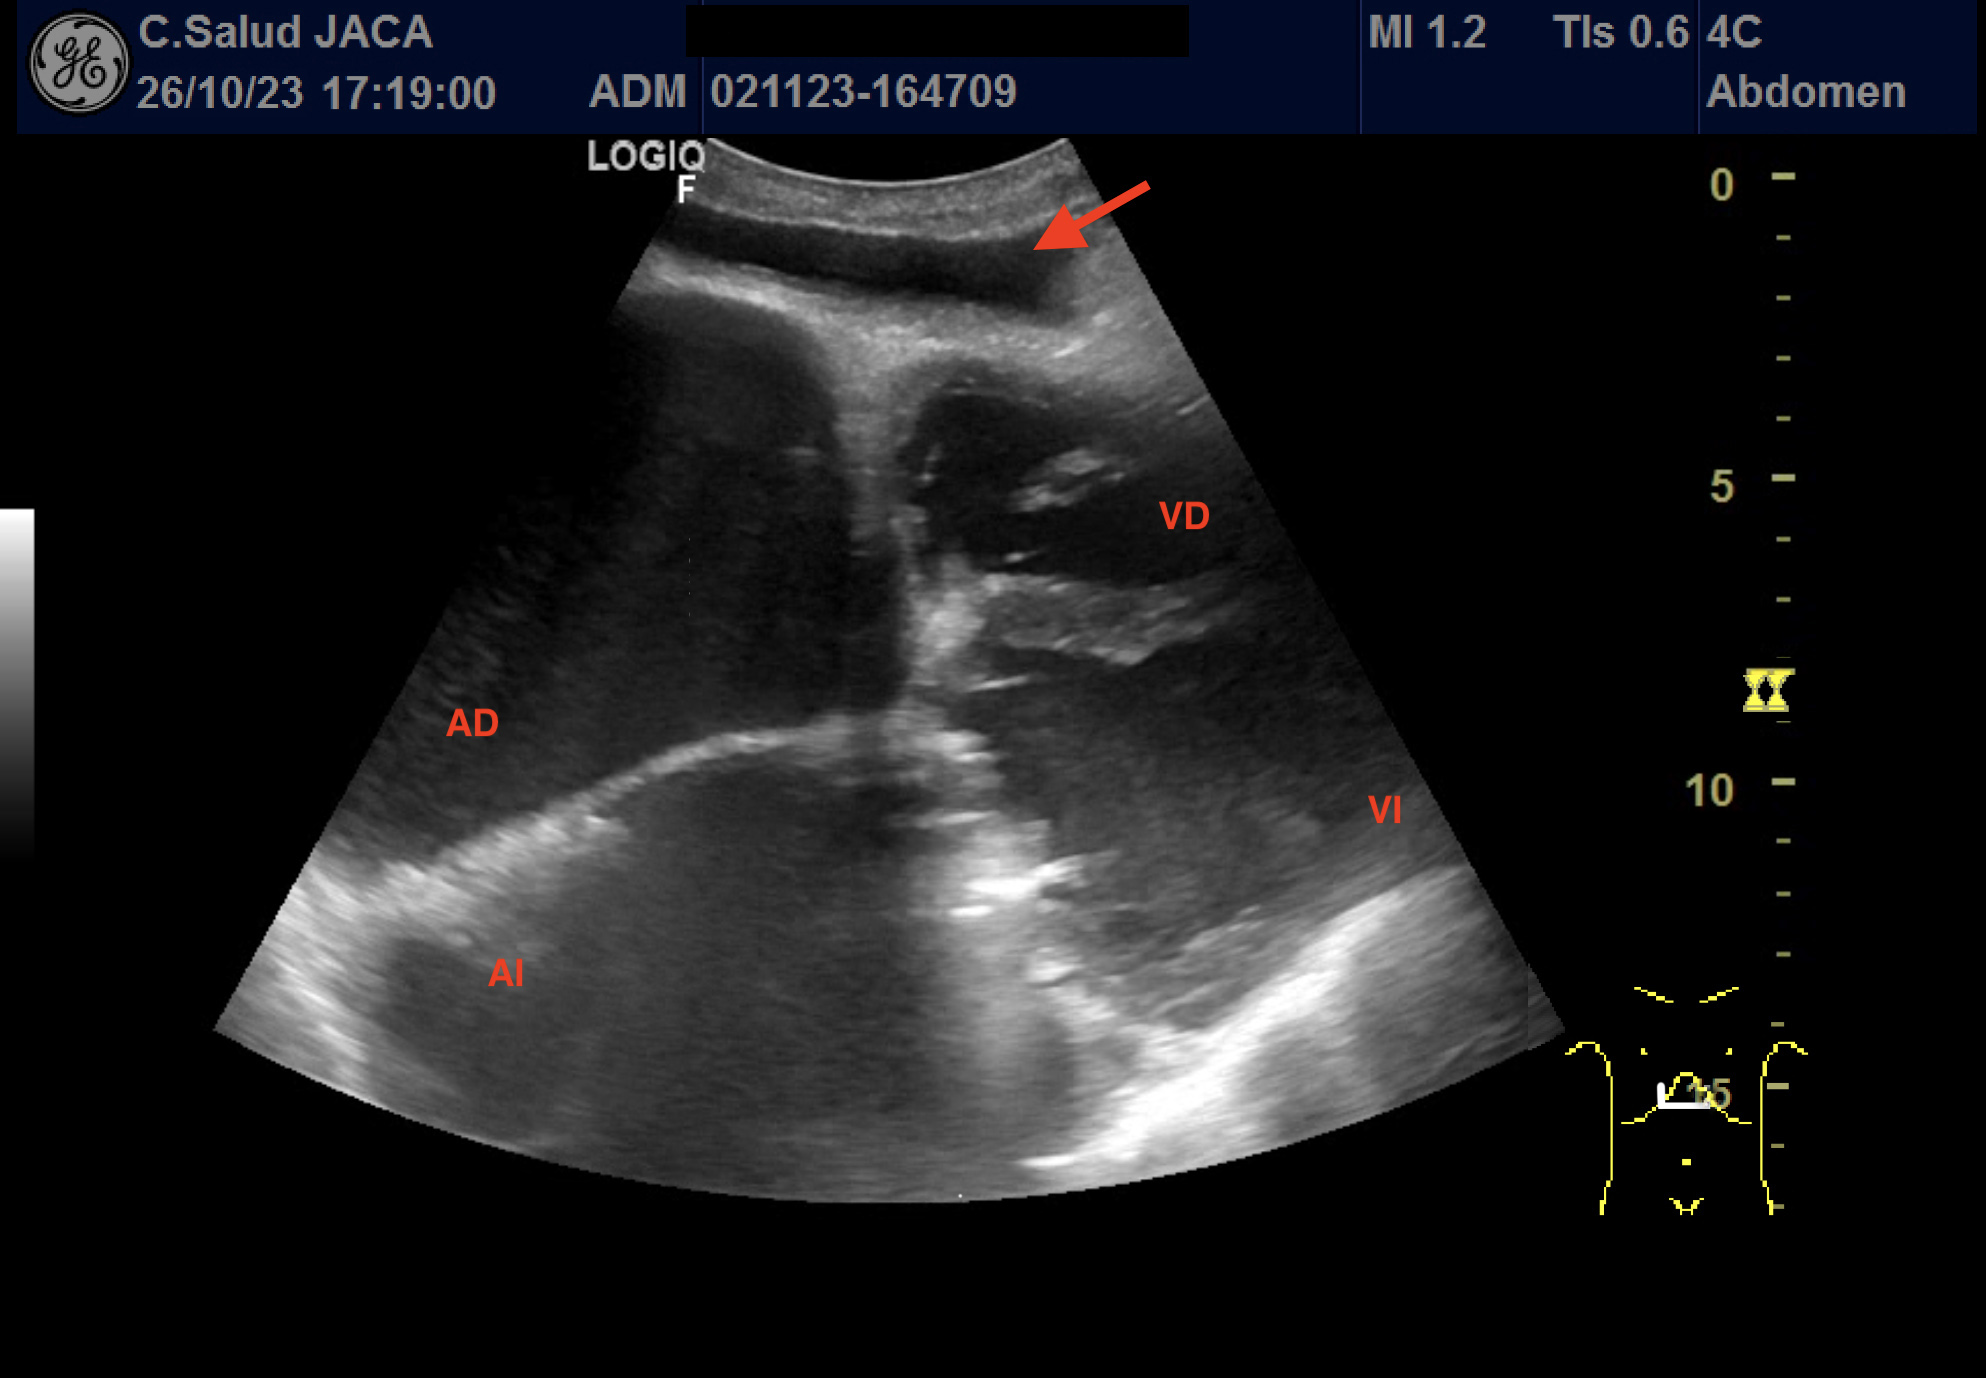

Presentamos las ilustrativas imágenes ecográficas obtenidas con sonda convex en la consulta de su Médico de Familia, que muestran derrame pleural y pericárdico, gran dilatación de ambas aurículas (ventana subxifoidea), ascitis, engrosamiento de 30 mm de la cava a su entrada en la aurícula derecha, que no se modifica con la inspiración, y congestión igualmente de las venas suprahepáticas.